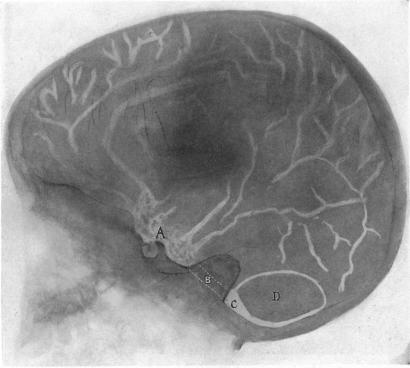

RONTGENOGRAPHY OF THE BRAIN AFTER THE INJECTION OF AIR INTO THE SPINAL CANAL.

Ann Surg. 1919 Oct;70(4):397-403. doi: 10.1097/00000658-191910000-00004.